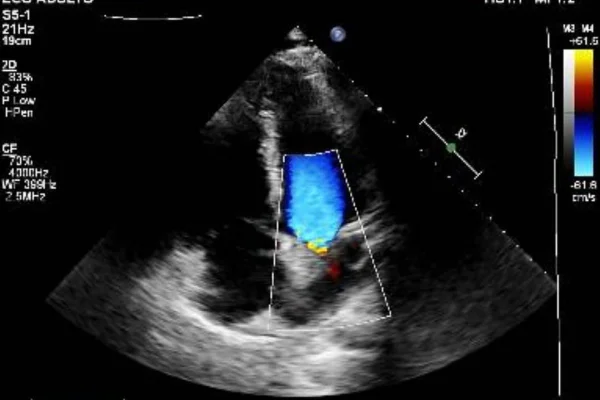

Em uma publicação, o influenciador mostrou exames que mostram a presença da bala no coração, além de imagens do veículo alvejado e da cicatriz no peito e na perna, onde também atingido.